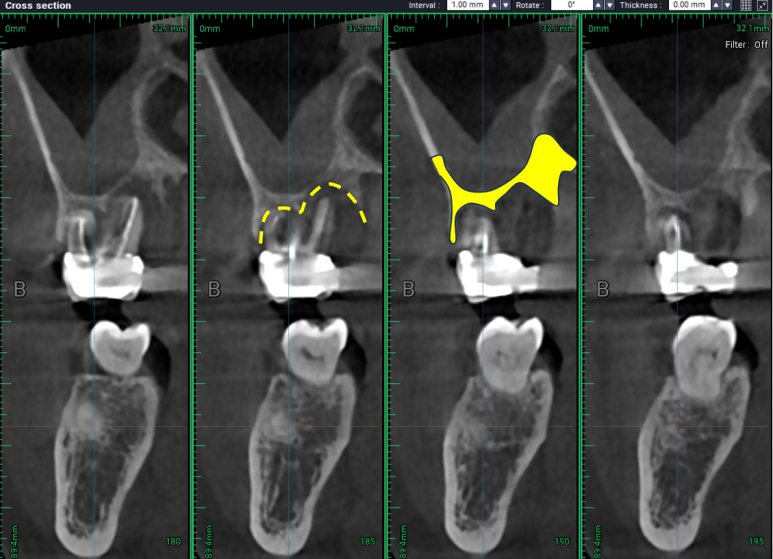

발치&뼈이식술 (치조제보존술) 전과

이를 뽑고 뼈이식을 한 뒤 4개월 쯤 지나서 치과용 CT를 비교해보면,

노란 선은 이를 뽑고 나서 잇몸뼈 하단의 위치, 노란면은 사용 가능한 잇몸뼈의 양.

치아가 있을 때,

염증이 가득해 대부분의 뼈가 없어져서 상악동 하연과 잔존한 치조골 사이의 뼈가 대부분 사라져있는 그 때와 달리,

노란 선은 임플란트를 심을 수 있는 잇몸뼈 상단의 위치, 노란면은 사용 가능한 잇몸뼈의 양.

임플란트를 제거하고 넉넉히 뼈이식을 해둔 결과, 4개월이 지난 시점에서 잇몸뼈가 가득한 듯한 모습!!

치과용 CT 상에서 모의 수술을 시행하였을 때, 임플란트가 위치할 수 있을만큼

잇몸뼈가 넉넉히 재생되었습니다.